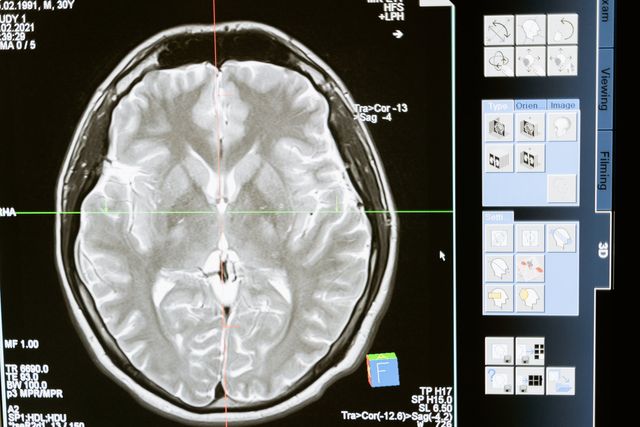

Navigate through our brain, spine and neurovascular pages to learn more about specific conditions and the innovative neurosurgery technology we use to treat them. Each page provides you with detailed information on tumors, strokes, spinal stenosis and more, with helpful links that can better inform you and your loved ones.

IGEA Brain, Spine, Pain & Orthopedics is a world-class center of neurosurgical excellence that delivers information for each field of practice to patients in New Jersey and across the nation. Select any category below to learn more about your condition and the leading edge surgical systems we use to help guide you into a state of health and well-being.